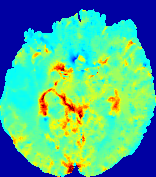

LesionRefer to captionRefer to captionRefer to captionRefer to captionRefer to captionRefer to caption𝐕rgbsubscript𝐕𝑟𝑔𝑏{\bf{V}}_{rgb}Refer to captionRefer to captionRefer to captionRefer to captionRefer to captionRefer to caption𝐕2subscriptnorm𝐕2{\|\bf{V}}\|_{2}Refer to captionRefer to captionRefer to captionRefer to captionRefer to captionRefer to captionRefer to caption3.53.53.52.82.82.82.12.12.11.41.41.40.70.70.70.00.00.0(mm/s)𝑚𝑚𝑠(mm/s)D𝐷DRefer to captionRefer to captionRefer to captionRefer to captionRefer to captionRefer to captionRefer to caption0.0200.0200.0200.0160.0160.0160.0120.0120.0120.0080.0080.0080.0040.0040.0040.0000.0000.000(mm2/s)𝑚superscript𝑚2𝑠(mm^{2}/s)Slice #1Slice #2Slice #3Slice #4Slice #5Slice #6

Figure 4: PIANO feature maps for another patient in the ISLES 2017 training set, where the lesion is located in the right hemisphere. Top row: segmented stroke lesion region (white) on different slices. The corresponding slices for the PIANO feature maps are shown in the following rows.

For a better insight into an estimated velocity field 𝐕𝐕{\bf{V}} and diffusion field 𝐃𝐃{\bf{D}}, we compute the following maps: (1) 𝐕rgbsubscript𝐕𝑟𝑔𝑏{\bf{V}}_{rgb}: Color-coded orientation map of 𝐕=(Vx,Vy,Vz)T𝐕superscriptsuperscript𝑉𝑥superscript𝑉𝑦superscript𝑉𝑧𝑇{\bf{V}}=(V^{x},V^{y},V^{z})^{T}, obtained by normalizing 𝐕𝐕{\bf{V}} to unit length and mapping its 3 components to red, green, blue respectively; (2) 𝐕2subscriptnorm𝐕2\|{\bf{V}}\|_{2}: 222 norm of 𝐕𝐕{\bf{V}}; (3) D𝐷D: scalar field in Eq. 5.

Fig. 3 and Fig. 4 show the PIANO feature maps estimated from two ISLES 2017 patients: all are highly consistent with the lesion in both cases. Details of the blood flow trajectories are revealed in 𝐕rgbsubscript𝐕𝑟𝑔𝑏{\bf{V}}_{rgb} by the ridged patterns and the sharp changes of colors in the unaffected (right) hemisphere, while the flat patterns appearing within the lesion provide little directional information about the velocity and indicate low velocity magnitudes. Velocity magnitudes are more directly visualized via 𝐕2subscriptnorm𝐕2\|{\bf{V}}\|_{2}, from which one can easily locate the lesion where 𝐕2subscriptnorm𝐕2\|{\bf{V}}\|_{2} is low. D𝐷D also indicates lower diffusion values in the lesion, though with less contrast potentially due to the fact that it captures the accumulated effect of CA diffusion at the voxel-level.